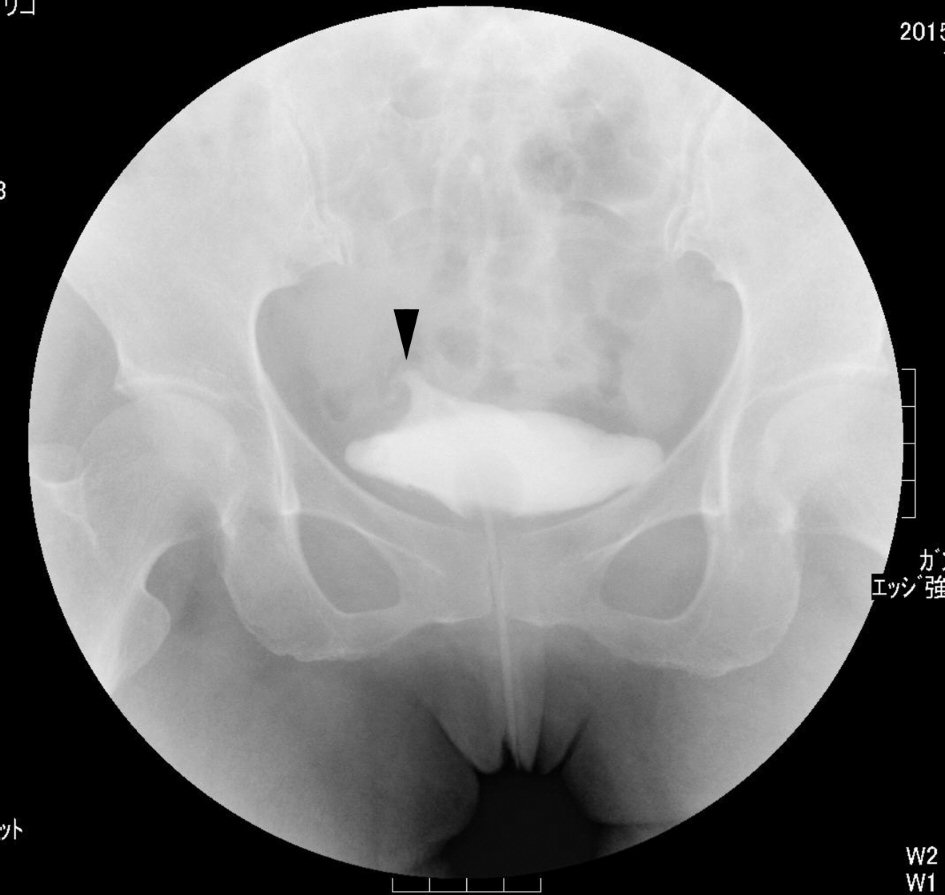

Three days after admission, cystoscopy revealed a small perforation on the right side of the bladder dome (Fig. 2a). The patient was diagnosed with intraperitoneal bladder rupture, and a renal pelvic balloon catheter was placed after cystoscopy. Four days after admission, a second non-contrast CT scan detected loss of fluid in the abdominal cavity (Fig. 1c). Five days after admission, a cystogram showed extravasation of contrast agent from the bladder dome (Fig. 3). Conservative management was continued because urine could be constantly drained and her general condition and laboratory data had improved.

![]() Click for large image | Figure 3. A conventional cystogram showed extravasation of contrast agent from the bladder dome (arrowhead) at 5 days after admission. |